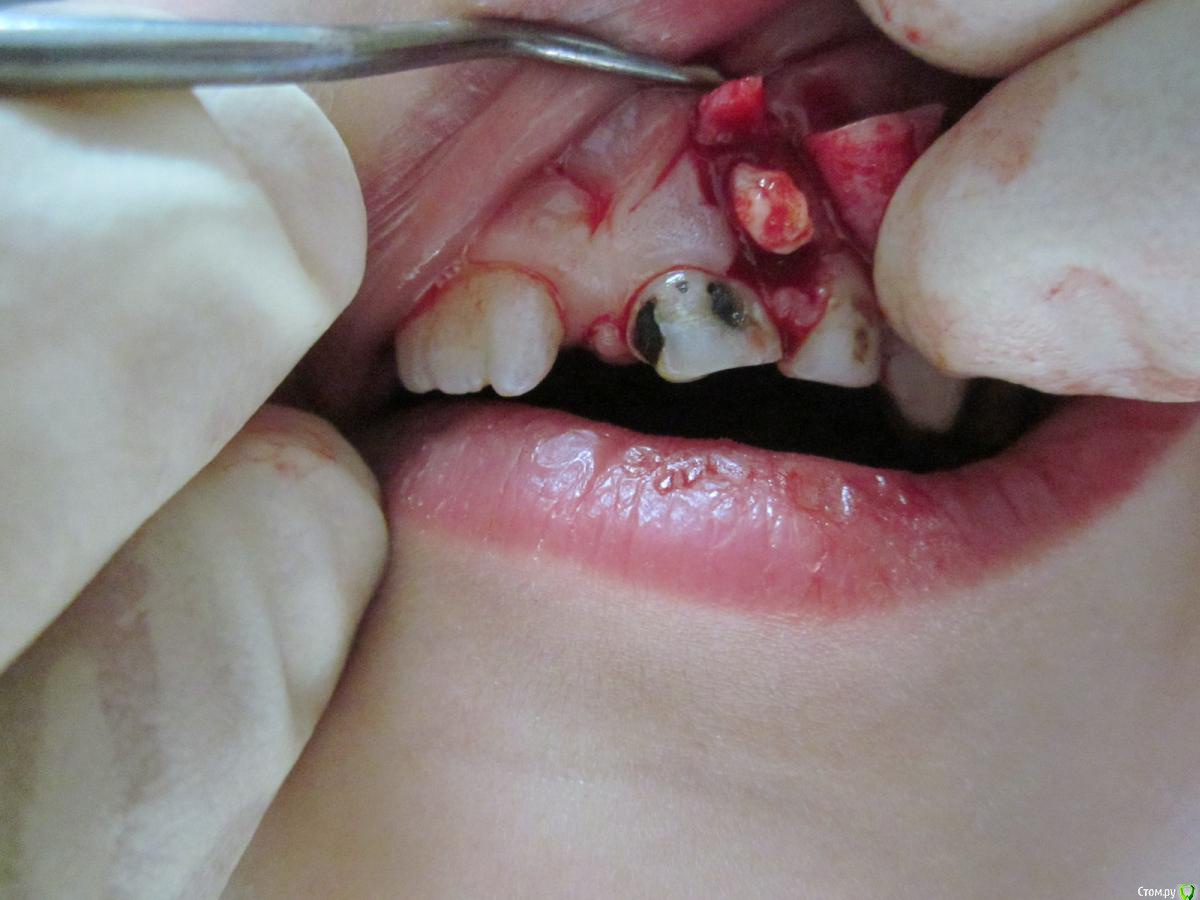

По данному случаю: пациент 6-7 лет, 21 не растёт, все динамят (ортодонты и терапевты), дошли до хирурга: на снимок прицельный, что то не то, на КТ охарактеризовал как одонтому. Операция под

анестезией Ультракаин дс, кортикальную пластинку трепанировал «расковырял» эскаватором, убрал конгломерат тведых тканей, саму оболочку, удалил 61. Биологический материал в пробирку с физ

раствором, направление на исследование в гистологию и ГОУ самим.

На перевязках ничего особенного, швы убрал на 7–е сутки, результаты анализов не принесли, и потом пропали. Прорезался 21 или не не знаю, вызвонивать не стал.